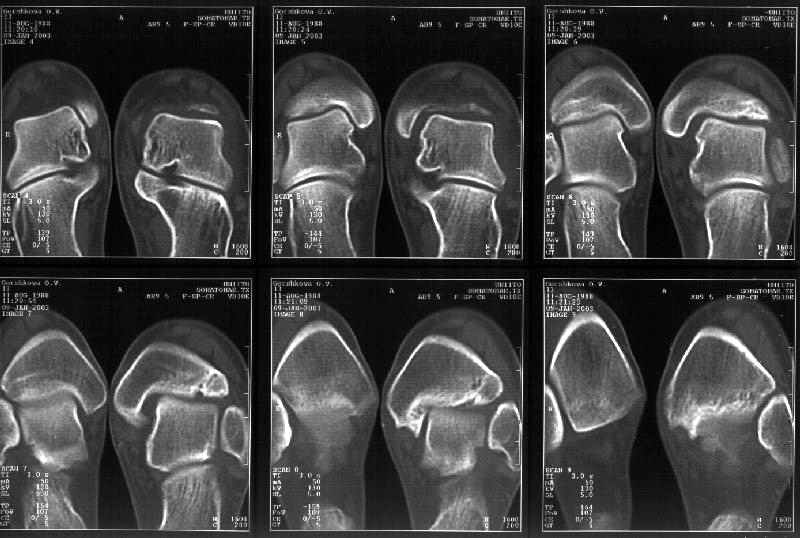

На КТ я попытался изобразить скромными своими способностями (А)- место перелома, (С)- нормальный суставной зазор меж тараном и тремя его маллеолами. (В)- образовавшийся в результате перелома широкий раза в три зазор, позволяющий, по-моему, сублюксацию тарана при ходьбе. В свете данных КТ, критически важных, я бы предложил вертикальную остеотомию места перелома

задне-внутренним подходом и фиксацию мед. маллеола прижатым к тарану с помощью тонкого compression screw. После этого гипсовый сапожок и немедленное расхаживание ноги.